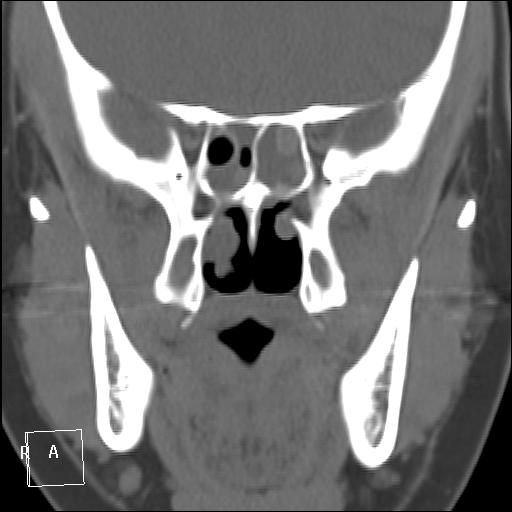

КТ ППН и носоглотки. Девушка 21 года. Полипозный риносинусит.

Госпитализирована для оперативного лечения. Удалены полипы носа. Вторым этапом планируется гайморотомия. Во время операции - подозрение на образование носоглотки. Сохраняется затруднение носового дыхания. Направлена на КТ. Категорически отказалась от контрастировния (лекарственная полиаллергия, боится).

Полип в носоглотке справа. Нарушена пневматизация придаточных пазух носа кроме левой решётчатой. В левой гайморовой на дне неясно что…

На дне гайморовой - полип, в носоглотке немаленький хоанальный полип. Там всё в полипах, а они и фиброзные бывают, и ангиофибромы, и ангиоаденомы... Вот и плотность разная.

Ну, как-то все в одну кучу - и полипы, и ангиофибромы. При ангиофиброме, например, околоносовые пазухи свободны. А гиперденсность более характерна для грибкового поражения (аспергилеза), в том числе и "севшим" на пломбировочный материал.

На операции визуально полипы аденоматозного типа. Какие будут гистологически после гайморотомии - сейчас трудно сказать. Если б гиперденсность была только по нижней стенке верхнечелюстной пазухи, тогда вариант с аспергиллезом на пломбировочном материале, на мой взгляд, был бы более вероятен. У девушки участки гиперденсности по всем стенкам верхнечелюстных пазух, в основной пазухе, совсем чуть - в решетчатом лабиринте слева, без костной деструкции. Без посева и гистологии - только гадать)). В носовой полости признаков грибкового поражения ЛОРы не отмечают. Но Вы правы, может иметь место изолированное поражение синусов.

Результаты гистологии после полипотомии носовой полости у нас: аденоматозные, миксоматозные полипы с признаками острого воспаления, фиброзные изменения стромы некоторых полипов. Из Твери пациентка еще не возвращалась, вестей о хоанальном полипе и результатов гайморо- и сфенотомии пока нет.